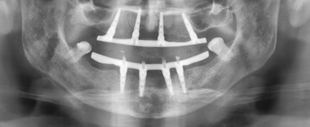

Clinical Case: Immediate Full-Arch-on-Four Rehabilitation with GDT RBM Implants

Clinical Case: Immediate Full-Arch Rehabilitation with All-on-4 Protocol Patient: 62-year-old male Procedure Date: July 2024 Case...